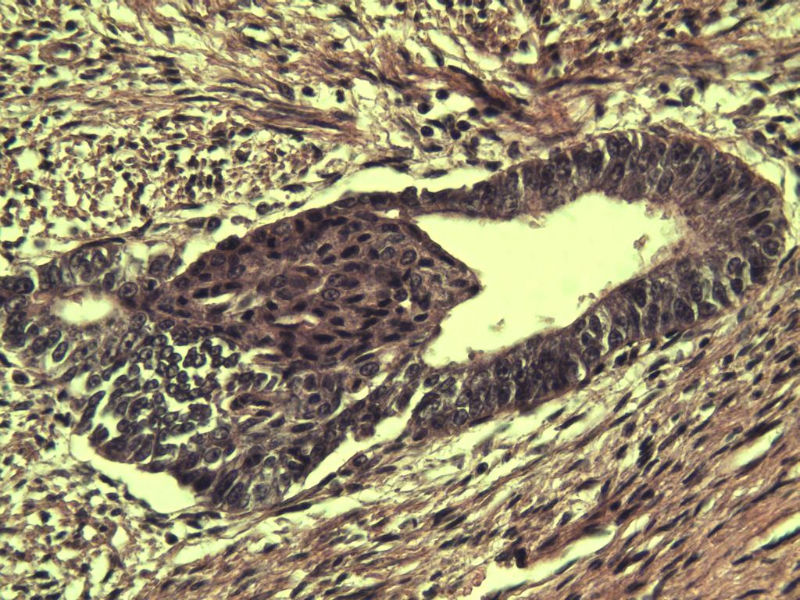

42岁 月经不规则一年 b超发现子宫肌瘤 行全子宫切除术  我取材时发现子宫颈管上段有一质地较硬区 2*1cm  请各位老师看看 是子宫内膜癌不? 谢谢了!

这是子宫颈管上段

子宫颈管上段图1

非癌,考虑子宫内膜异位症或腺肌瘤

肌层内腺体的特点:1、无内膜间质。

2、有鳞化。

3、无异型。所以应该还是个良性病变

非典型性息肉样腺肌瘤。

诊断依据:

1.临床特征:主要发生在绝经前女性,中位年龄39岁,大多数伴有月经紊乱。

2.大体特征:最常见于子宫下段,平均大小为直径2cm,表现为圆形,凸出于表面。息肉样的本质不总是很明显,也有无蒂和广基的肿瘤。

3.镜下特征:上皮成分由杂乱无章排列的不规则的子宫内膜型腺体构成,可以是立方形到矮柱状或假复层。显示有广泛的鳞化区域(本例图11-17均显示鳞化),表现为圆形的“桑葚”(图16-17);间质主要由平滑肌构成,且混有纤维组织。